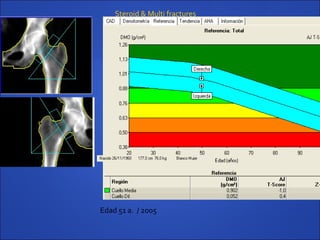

 Paciente varon 53 años, con antecedentes de (LES) lupusPaciente varon 53 años, con antecedentes de (LES) lupus

eritematoso sistemico en tratamiento a largo plazo coneritematoso sistemico en tratamiento a largo plazo con

dosis altas de prednisonadosis altas de prednisona

 T-score columna Lumbar -1.6T-score columna Lumbar -1.6

 T-score Cuello femoral -1.0 ( 2005)T-score Cuello femoral -1.0 ( 2005)

 T-score cuello femoral -1.6 ( 2007)T-score cuello femoral -1.6 ( 2007)

Edad 51 a. / 2005